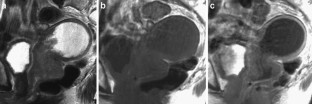

The endometrial cavity may demonstrate various imaging manifestations such as normal, reactive, inflammatory, and benign and malignant neoplasms. We evaluated usual and unusual magnetic resonance imaging (MRI) findings of the uterine endometrial cavity, and described the diagnostic clues to differential diagnoses. Surgically proven pathologies of the uterine endometrial cavity were evaluated retrospectively with pathologic correlation. The pathologies included benign endometrial neoplasms such as endometrial hyperplasia and polyp, malignant endometrial neoplasms such as endometrial carcinoma and carcinosarcoma, endometrial–myometrial neoplasm such as endometrial stromal sarcoma, pregnancy-related lesions in the endometrial cavity such as gestational trophoblastic diseases (hydatidiform mole, invasive mole and choriocarcinoma) and placental polyp, myometrial lesions simulating endometrial lesions such as submucosal leiomyoma and some adenomyosis, endometrial neoplasms simulating myometrial lesions such as adenomyomatous polyp and endometrial lesions arising in the hemicavity of a septate/bicornate uterus, and fluid collections in the uterine cavity (hydro/hemato/pyometra). It is important to recognize various imaging findings in these diseases, in order to make a correct preoperative diagnosis.